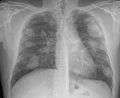

For uncomplicated silicosis, chest x-ray will confirm the presence of small (< 10 mm) nodules in the lungs, especially in the upper lung zones. Using the ILO classification system, these are of profusion 1/0 or greater and shape/size "p", "q", or "r". Lung zone involvement and profusion increases with disease progression. In advanced cases of silicosis, large opacity (> 1 cm) occurs from coalescence of small opacities, particularly in the upper lung zones. With retraction of the lung tissue, there is compensatory emphysema. Enlargement of the hilum is common with chronic and accelerated silicosis. In about 5-10% of cases, the nodes will calcify circumferentially, producing so-called "eggshell" calcification. This finding is not pathognomonic (diagnostic) of silicosis. In some cases, the pulmonary nodules may also become calcified.

Complicated silicosis

Silicosis ILO Classification 2-2 R-R